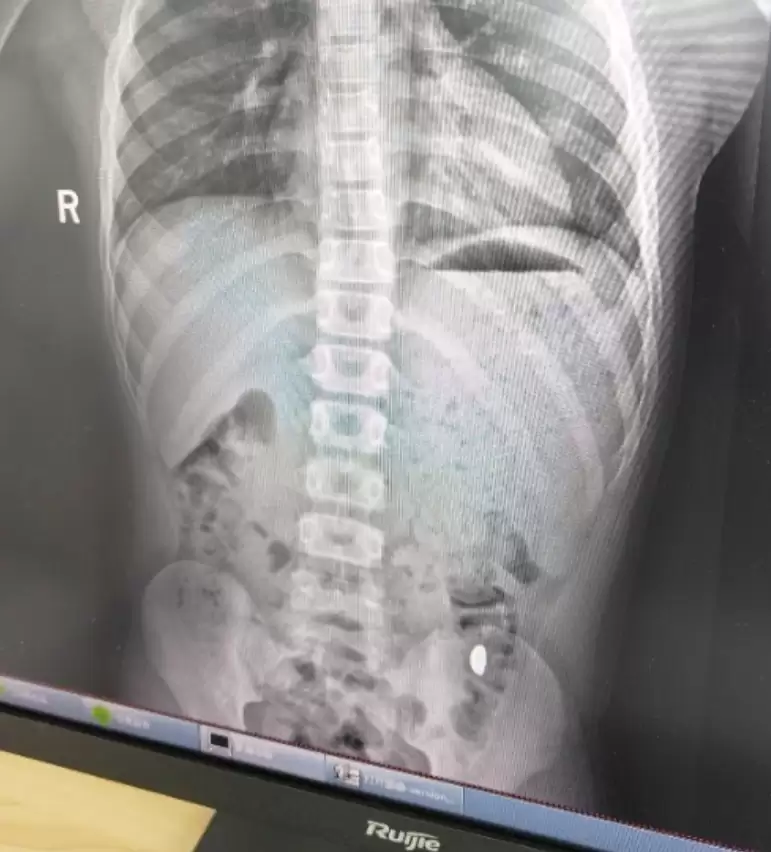

经检查发现,孩子吞下去的黄金碎片已经进入大肠,目前没有造成堵塞或划伤消化道的情况,暂时无大碍

医生叮嘱刘女士,接下来几天一定要密切观察孩子的排便情况,确认碎金是否能随粪便排出,同时还要按时带孩子复查,有任何不适要立刻就医。